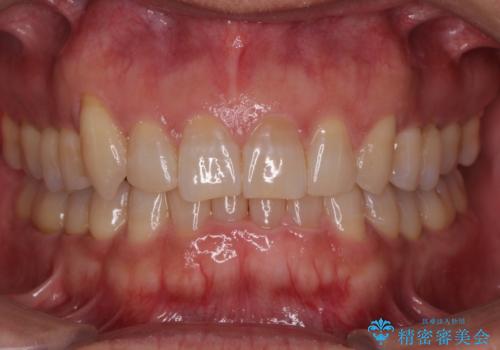

上顎前歯のデコボコを改善してスッキリした口元に ワイヤー装置での非抜歯矯正